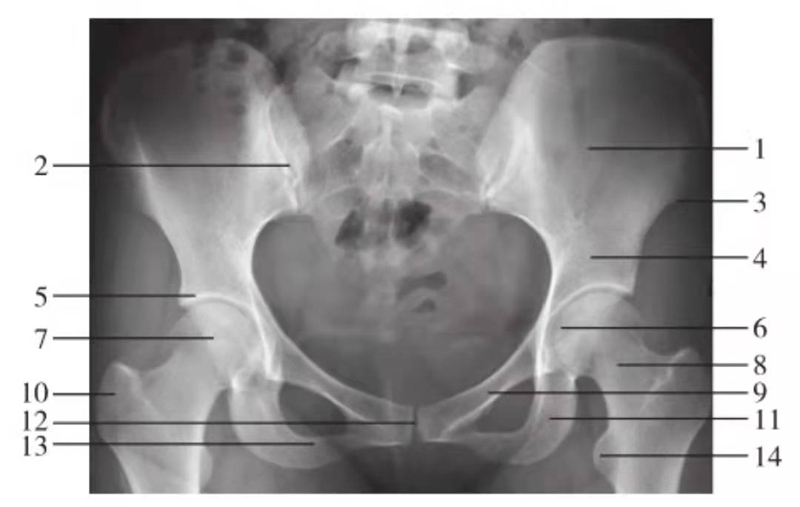

骨盆前后位

图6 骨盆正位

1.髂骨翼;2.骶髂关节;3.髂前下棘;4.髂骨体;5.髋臼顶;6.股骨头凹;7.股骨头;8.股骨颈;9.耻骨上支;10.大转子;11.坐骨支;12.耻骨联合;13.耻骨下支;14.小转子